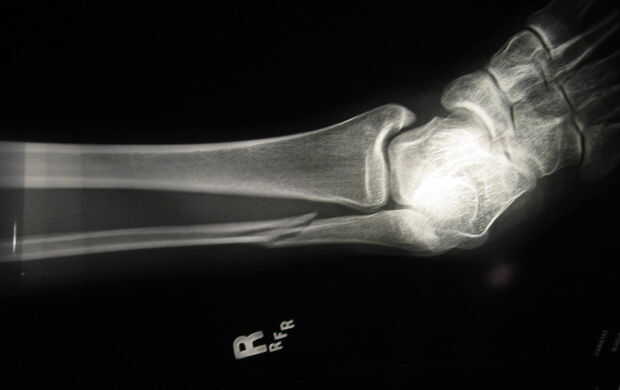

Tomó mucho tiempo para paramédicos demostrar para arriba. Eran ásperos y deseábamos que nos habíamos mudado su nosotros mismos. Aquí le damos la pierna después de que los paramédicos crueles arrancó lo nuevo de en forma de pierna.